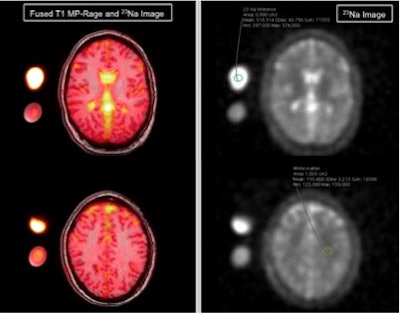

Dr. Melissa Meyer and colleagues from University Hospital Mannheim and Heidelberg University in Heidelberg, Germany, performed cerebral sodium MRI exams on healthy subjects and patients being clinically evaluated for migraine. They found that migraine patients had significantly higher sodium concentrations in the cerebrospinal fluid than those who did not have migraines.

The researchers recruited 12 women with a mean age of 34 who had been clinically evaluated for migraine. In addition, 12 healthy women of similar ages were added to the study to serve as a control group. The women who were being assessed for migraine filled out a questionnaire regarding the length, intensity, and frequency of their migraine attacks and accompanying auras. After both the migraine patients and healthy controls received cerebral sodium MRI exams, the researchers compared the sodium concentrations in both groups of women.

They found that migraine patients had significantly higher sodium concentrations in the cerebrospinal fluid, according to the RSNA. No statistically significant differences were found between the two groups in terms of sodium concentration in the gray and white matter, brain stem, and cerebellum.